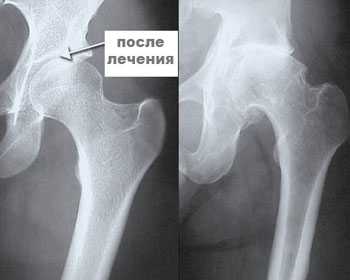

Артроз тазобедренного сустава 3 стадия. В операции отказали ввиду возраста и большого веса. Плазмацитоферез восстановил сумку сустава, произошло восстановление суставного хряща и продукции смазочной жидкости сустава. Курс - 7 дней.